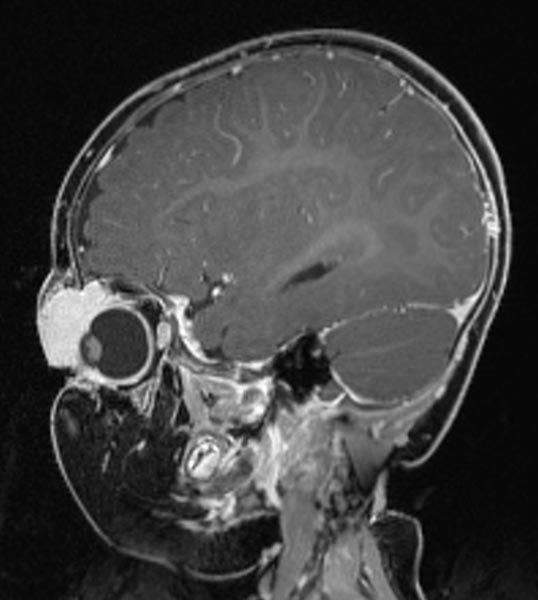

T1-weighted, coronal MRI after contrast depicts a homogeneous, strong enhancement in a solid, sharply demarcated tumor of the left eye. This is suggestive of an infantile hemangioma as part of the spectrum of vascular tumors.

T1-weighted coronal plane MRI after contrast administration in a slightly more dorsal plane shows extension of the contrast-enhancing solid mass well into the medial orbit of the left eye with displacement of the eyeball caudally and laterally.